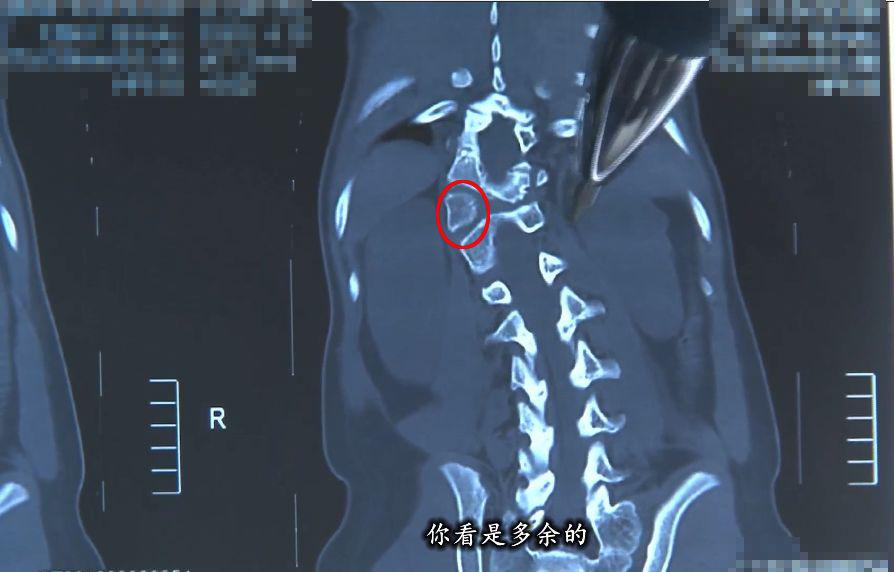

脊柱側彎,即脊柱向側方彎曲——正常人的脊柱從正面看是直的,而脊柱側彎患者的脊柱從正面看是呈字母「C」形或者「S」形的。

由于人體的脊柱是三維結構,從三維上看,脊柱側彎會伴有脊柱結構的旋轉,是一種三維的脊柱畸形。

為了進一步查明塔吉脊柱側彎的真相,伊力為她做了站立位脊柱全長 X 線片檢查。

從 X 線片中可以看出,塔吉的脊柱有明顯的側彎。